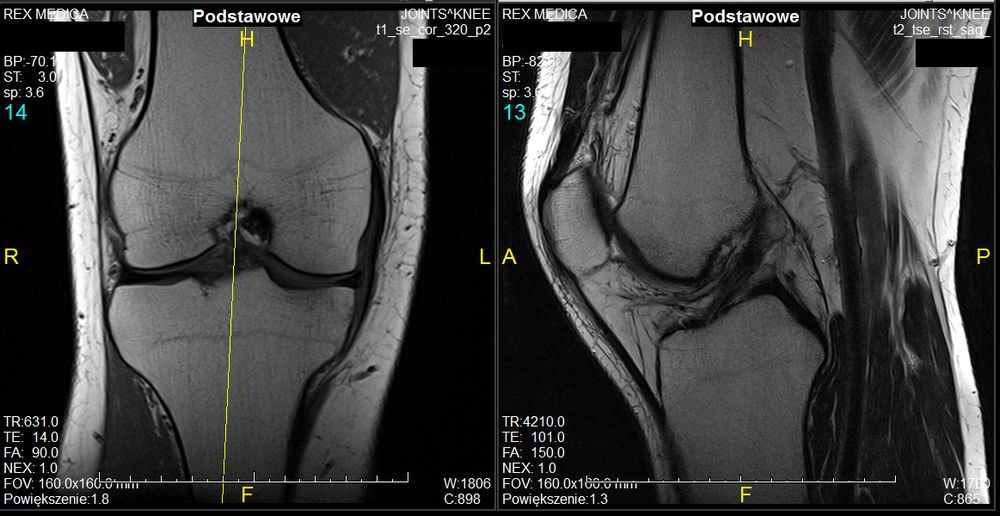

Aby jak najdokładniej zdiagnozować dolegliwości związane z kolanem, w możliwie najwcześniejszej fazie, wykonać należy badanie za pomocą rezonansu magnetycznego. Jednym z takich miejsc, gdzie można to zrobić, jest warszawskie Centrum Rezonansu Magnetycznego Rex Medica. Wskazaniem są dolegliwości bólowe, opuchlizny, guzy, choroby zwyrodnieniowe, a także urazy skrętne czy przeciążeniowe.

Za pomocą tego aparatu zobrazować możemy strukturę więzadeł, ocenić ich ciągłość i położenie, a następnie wskazać ewentualne uszkodzenia. Ocenie podlegają również łąkotka boczna i przyśrodkowa. Dzięki badaniu rezonansem magnetycznym można określić typ rzepki, jej położenie, a także kąt chrzęstny wcięcia udowego, jaki tworzy rzepka i kość udowa. Pozwala wykryć też patologię ciała Hoffy.

Za pomocą tego badania można jak najszybciej wykryć chondromalację, co jest szczególnie ważne, bo chrząstki nie są unaczynione i ich powrót do pełnej sprawności w procesie regeneracji jest w zasadzie niemożliwy. Urządzenie pozwala zobrazować również zwykle, bolesne, obrzęki szpiku kostnego.